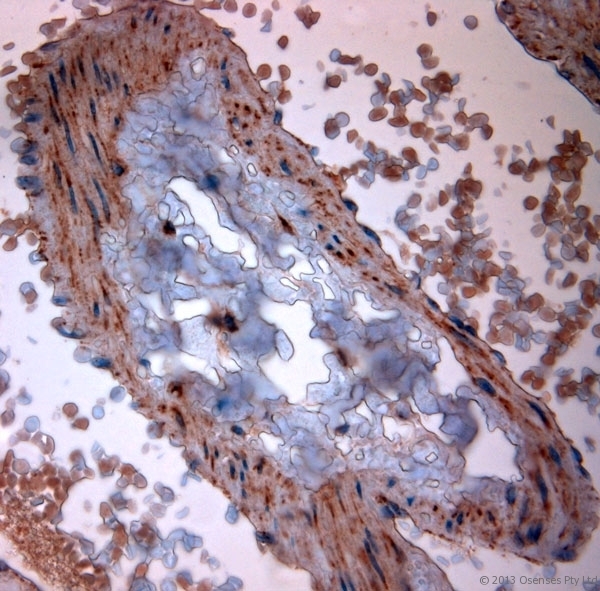

- Rabbit antibody to TPC2 (700-752). IHC-P on paraffin sections of human lung. HIER: Tris-EDTA, pH 9 for 20 min using Thermo PT Module. Blocking: 0.2% LFDM in TBST filtered through a 0.2 micron filter. Detection was done using Novolink HRP polymer from Leica following manufacturers instructions. Primary antibody: dilution 10 ug/ml, incubated 30 min at RT using Autostainer. Sections were counterstained with Harris Hematoxylin.